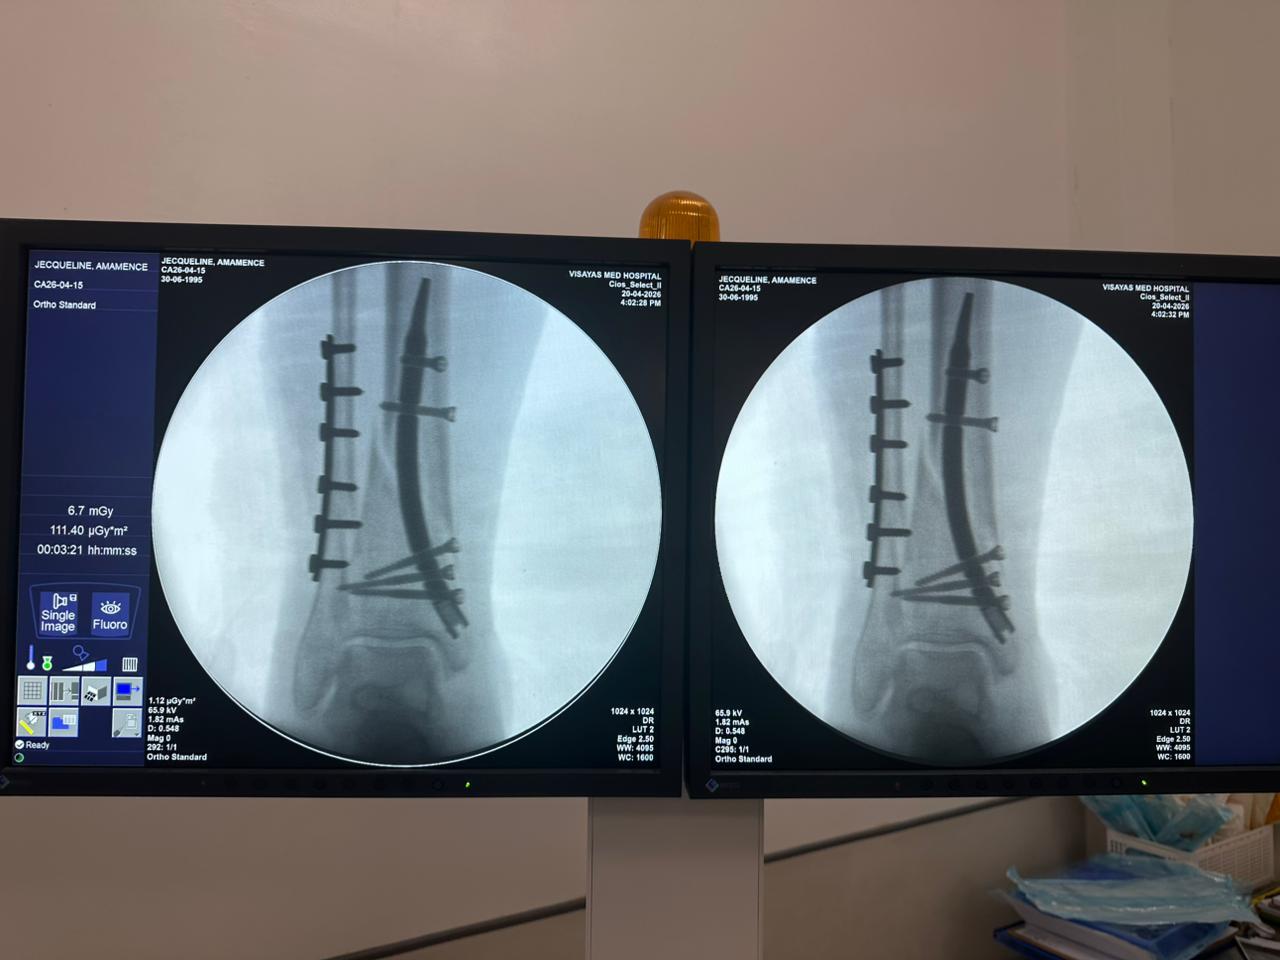

Estudio de caso de fijación de clavo tibial distal con soporte de placa para peroné

Tibia y peroné distales

Clavo tibial distal

Placa de bloqueo del peroné

Radioscopia intraoperatoria con arco en C, vistas AP y lateral

Este caso involucró la fijación de la tibia distal utilizando un clavo tibial distal intramedular. La fluoroscopia intraoperatoria confirmó la posición del clavo, los tornillos de bloqueo distales y la fijación de la placa del peroné.

clavo-tibial-distal-fluoroscopia-intraoperatoria-CZMEDITECH (4)

clavo-tibial-distal-fluoroscopia-intraoperatoria-CZMEDITECH